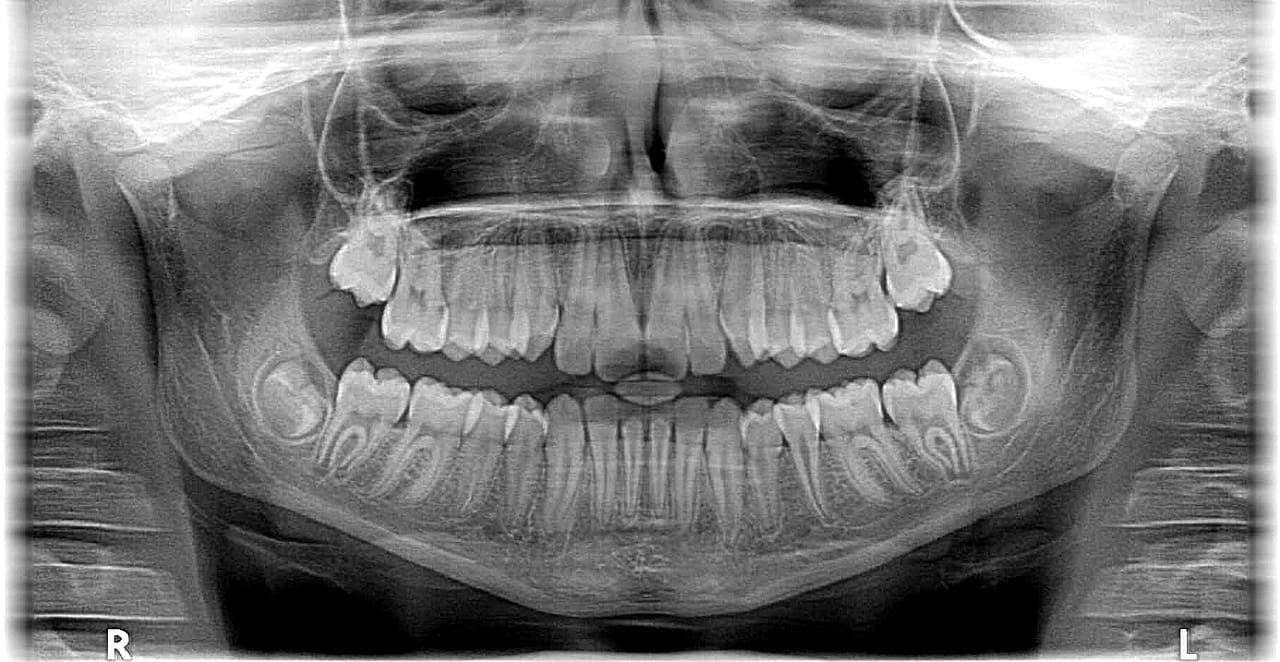

Dental X-rays:

Taking X-rays reveals conditions that cannot be seen by naked sight, including the state of teeth between and below the gum line.